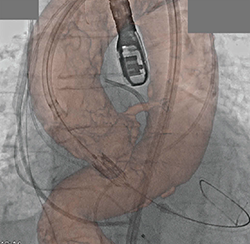

そこで当社では,ステント強調モードとして専用のX線条件と画像処理を考案することで,バルーンマーカーも画像固定も必要とせずに,ステント強調画像を提供可能とした(図4)。このモードは,撮影プログラムの切り替え作業のみで通常と同じ感覚で撮影可能であり,リアルタイムに画像を描出することができるため,ステントの位置決めやステント留置後の追加拡張の際などに有効に活用されている。

図4 PCIサポートアプリケーション:

ステント強調モード

画像中のステントは「XIENCE Alpine」

(アボット社製)